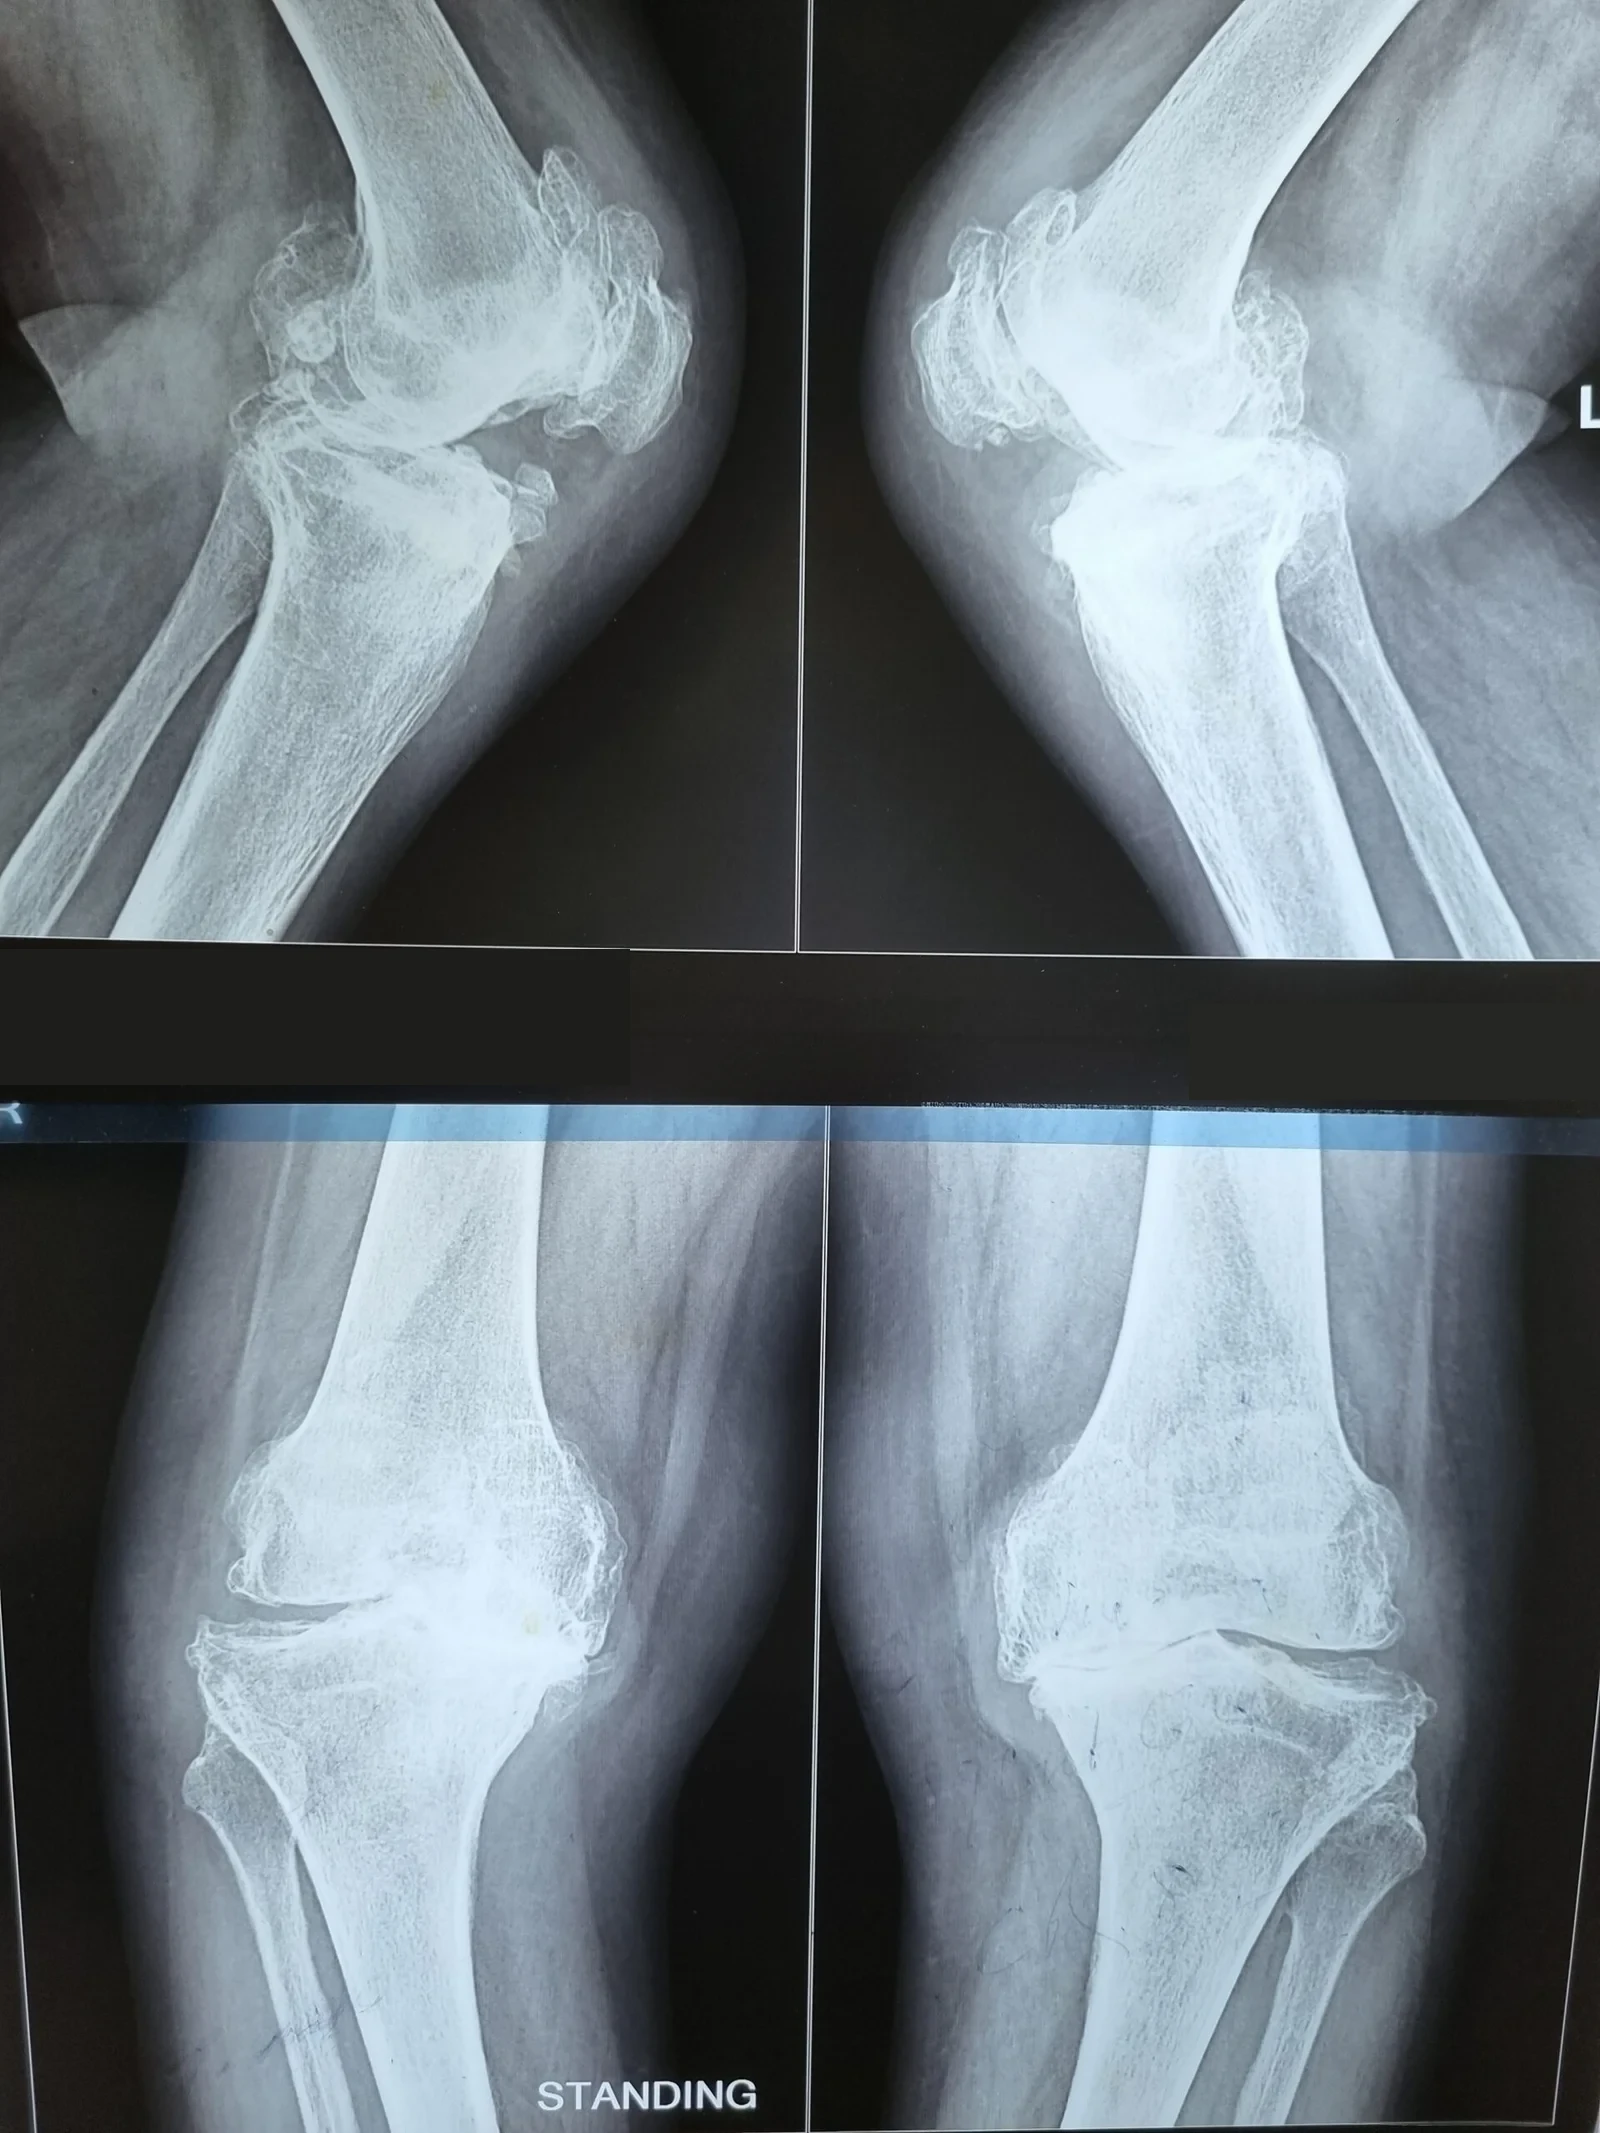

Pre-Op X-Ray

Stiff Knee with Flexion Contracture & Rigid Varus